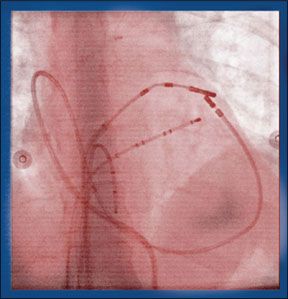

For patients with atrial fibrillation (AFib), a condition in which the heart beats irregularly, medication can often return the heart to its normal rhythm. But when medication is ineffective, AFib may require ablation-a procedure that entails going into the heart and stopping the abnormal electrical impulses that create the irregular heartbeat. The most common method of performing this procedure is called catheter ablation, in which a catheter-a thin, flexible tube-is threaded to the heart through the femoral vein via a small incision in the leg or groin. However, for patients who are not candidates for the procedure or in whom it is not succesful, another method called epicardial ablation is emerging as an alternative. "Patients with left atrial enlargement, long-standing persistent AFib, and anatomic barriers like abnormal veins in the leg are good candidates for epicardial ablation but not catheter ablation," says Marc Gillinov, MD, a cardiac surgeon at Cleveland Clinics Heart & Vascular Institute. "While epicardial ablation is performed on a small percentage of people with AFib, its a small percentage of a large number of people who otherwise have no treatment options."